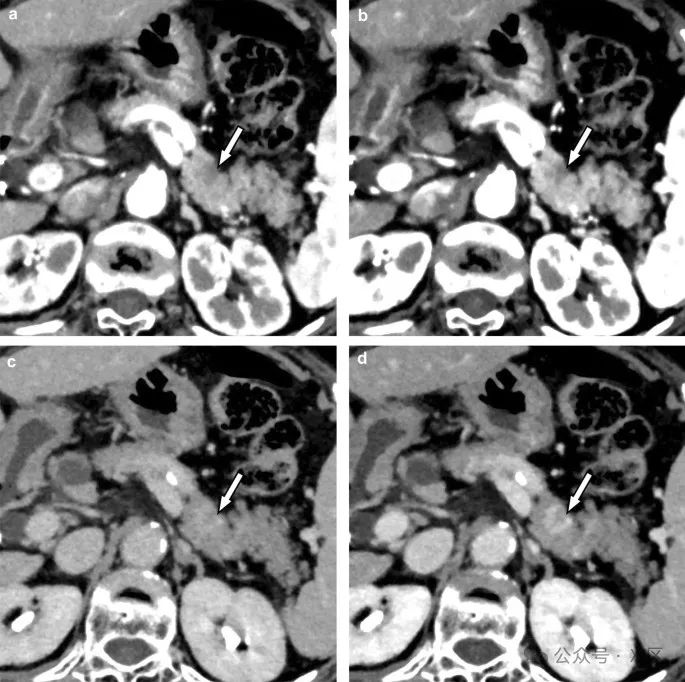

增强CT也在血栓诊断中有用。通过光子计数CT,即使是小血栓也能清晰可见,有助于准确诊断。

图11 肠系膜静脉中的小血栓(箭头)在光子计数CT图像上可见,分别为70 keV(A)和50 keV(B)。50 keV图像(B)显示血栓的对比度高于70 keV图像(A)。光子计数CT在静脉血栓的可视化方面表现出色。挑战